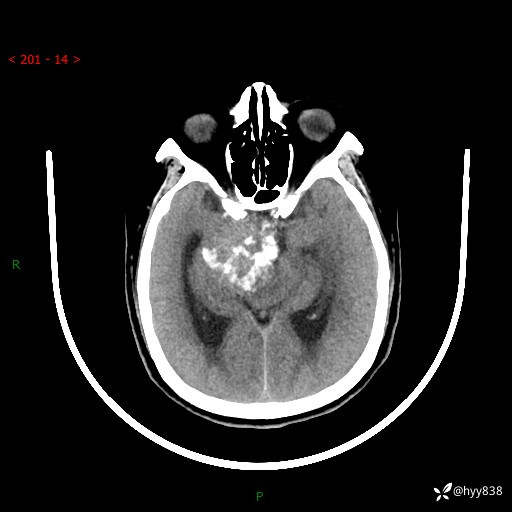

颅脑CT平扫